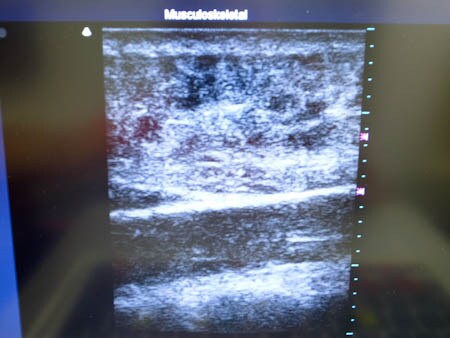

いつものように3Dタッチビュー(超音波)で

皮下脂肪層を評価してみましょう。

右二の腕

↓ ↓ ↓

上の画像の部分の皮下脂肪層をつまんでみましょう。

同様に左二の腕 ↓ ↓ ↓